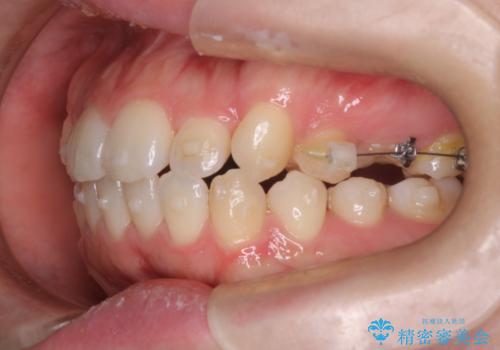

- 患者様は歯並びの乱れを気にされて来院されました。特に小臼歯の捻転(ねじれ)が強く、見た目だけでなく噛み合わせにも影響がありました。できるだけ目立たない方法を希望されていたため、インビザライン(マウスピース矯正)を基本としつつ、より精密な動きが必要な部分にはワイヤー矯正を併用する計画を立てました。また、小臼歯の捻転については**部分矯正(MTM:Minor Tooth Movement)**を取り入れ、効率的に改善を目指しました。

まず、全体の歯並びを整えるためにインビザラインを使用し、徐々に理想的な位置へと歯を移動させました。一方で、ねじれの強い小臼歯に対しては、**部分的なワイヤー矯正(MTM)**を行い、より精密なコントロールを実施。約2年の治療期間を経て、歯並びと噛み合わせが整い、見た目の美しさだけでなく、機能的な改善も達成しました。患者様からは「自然な仕上がりで、自信を持って笑えるようになった」と喜びの声をいただきました。